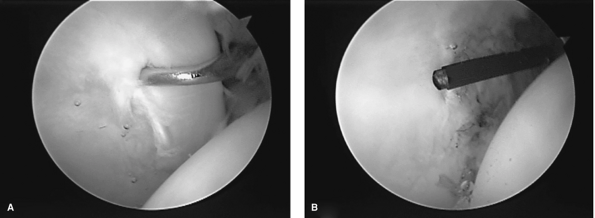

Arthroscopy provides excellent visualization and access to the

acetabular labrum (Fig. 8-2A, B).

Figure 8-2 A:

Tears of the acetabular labrum often occur at the junction of the labrum and the articular cartilage of the acetabulum. The distracted femoral head is visible at the right of the field. B: Flexible thermal ablation probes are quite useful in resection of degenerative labral tears. |